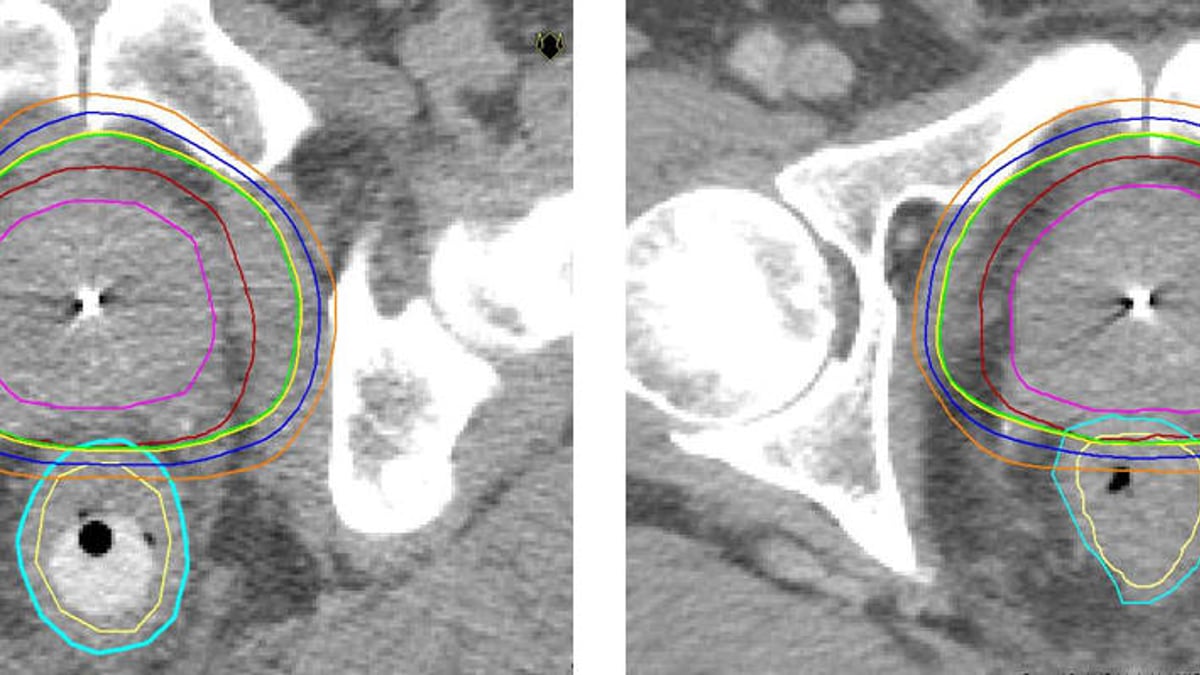

2005 var Akademiska pionjär i Sverige med strålbehandling med rektalstav mot prostatacancer. Sjukhuset är fortfarande ensamt om att erbjuda denna form av strålbehandling som ger färre biverkningar än andra jämförbara metoder. Metoden gör det möjligt att ge högre dos i prostata och skona frisk vävnad/intilliggande organ.

– Precis som vid annan strålterapi är målet med stavbehandling att döda cancercellerna. Vi behandlar 25-30 patienter per år med denna metod. Fördelen är att man kan öka avståndet mellan prostata och ändtarmen och därigenom ge högre stråldos i prostata och lägre i ändtarmen så att frisk vävnad skonas. Jämfört med konventionell strålbehandling utan rektalstav, som är vanligast idag, kan man ge lite högre stråldos utan fler biverkningar, säger Kristina Nilsson, överläkare i onkologi vid Akademiska sjukhuset.

Strålning är ett vanligt sätt att behandla prostatacancer, både när cancern är kvar i prostatan och när den spridit sig till andra delar av kroppen. Vid tidig sjukdom, när tumören inte spridit sig utanför prostatakörteln, är strålning ett likvärdigt alternativ till kirurgi som botande behandling. Forskning har visat att ju högre stråldoser man kan ge tumören, desto större är chansen till bot. De doser som fortfarande användes för något decennium sedan var ofta inte tillräckligt höga för att bota patienten. Det finns nu en stark strävan att utveckla metoder som gör att man kan öka stråldosen utan att förvärra biverkningarna.

En utmaning vid prostatacancer är precisionen eftersom prostatakörteln är rörlig, men strålningstekniken har successivt blivit allt mer träffsäker. Man skiljer på yttre strålning (strålkällan är utanför patientens kropp) som t ex strålbehandling med rektalstav, eller olika typer av intern strålbehandling, så kallad brachyterapi.

* Rektalstaven förs in i ändtarmen som trycks nedåt och separeras från prostatan. På så sätt kan stråldosen minskas till ändtarmen.